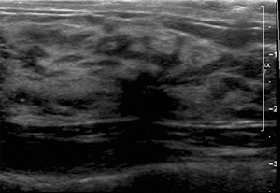

45 year old asymptomatic woman had a Screening Mammogram and was advised to return for Whole Breast Ultrasound Screening because of her breast density and maternal history of breast cancer at age 54.The mammogram shows marked fibrocystic change with multiple microcalcifications and cysts, but no suspicious findings. Whole Breast Ultrasound Screening showed numerous less than 1 cm cysts, and also an 11 mm suspicious, spiculated mass at 12:00 on the right.

Single frame from Whole Breast Ultrasound Screening study showing a spiculated mass in the right breast.